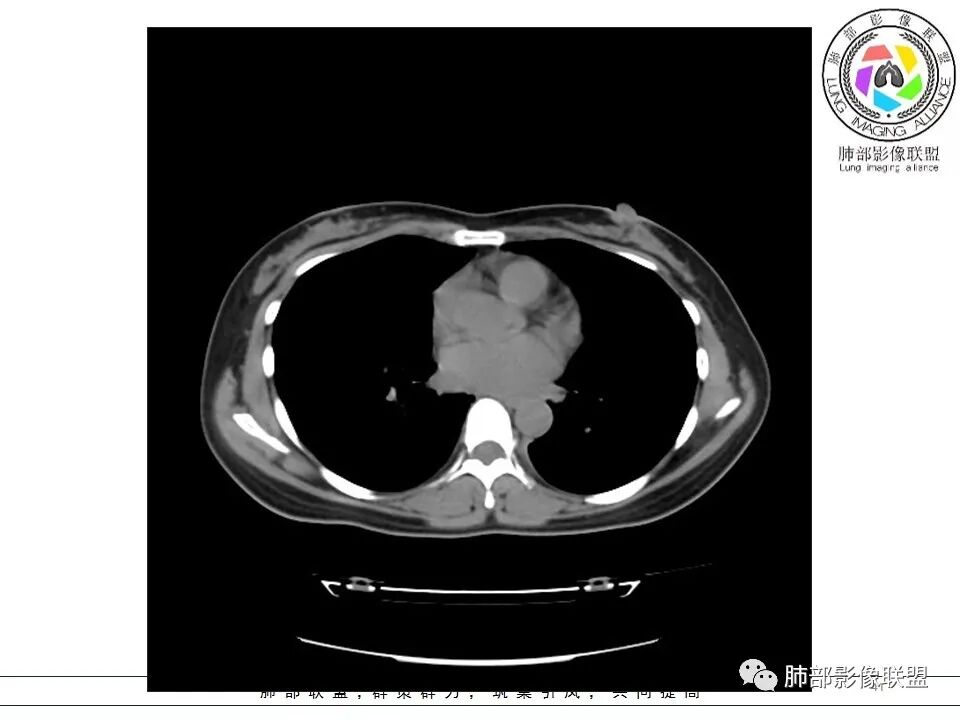

女,38岁,无症状,胸片体检发现两肺可疑病灶。

?其母亲有肺大泡,2017年手术。影像学特点:两肺胸膜下多发的大小不等囊状气腔,壁很薄或无可见的囊壁,小囊的边界比较清楚,大囊的形态比较怪异,以两下肺为著。考虑肺组织细胞增生症,鉴别肺淋巴管肌瘤病。

1、多发肺囊肿,双侧基底部,有或无自发性气胸。

BHD主要影像表现特征:    1、两肺内肺囊肿:80%以上的BHD患者会出现肺内囊肿,且倾向于基底部近胸膜下分布,特别是纵膈侧肺膜下,囊肿形状不规则、囊肿可大可小,肺内囊肿多毗邻肺下动脉或静脉近端,胸部CT上囊肿分布和特点对诊断有提示意义。    2、继发自发性气胸:BHD患者发生气胸风险是正常人的5倍,BHD患者的气胸发生率约为 1/4,气胸复发率则高达59%。   3、肾肿瘤:(常为双侧性、倾向于嫌色细胞组织学亚型)   4、皮肤表现(为面、颈部纤维性毛囊瘤、毛盘瘤)